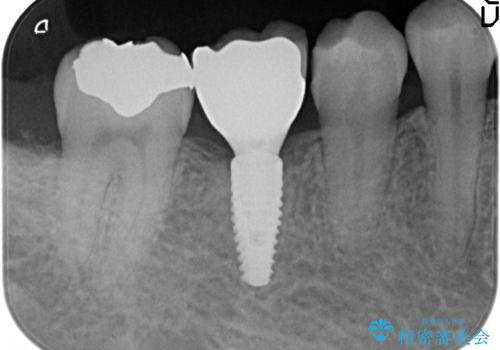

- 右下の奥歯にインプラントを入れたいと来院。

抜歯から時間が経っており、骨が十分あったためすぐにインプラントを入れることが可能でした。骨も補う必要がありませんでした。

インプラントの術式は比較的単純で、難しくないですが、予後を見据えて角化歯肉を増やす手間をかけることが大変重要です。